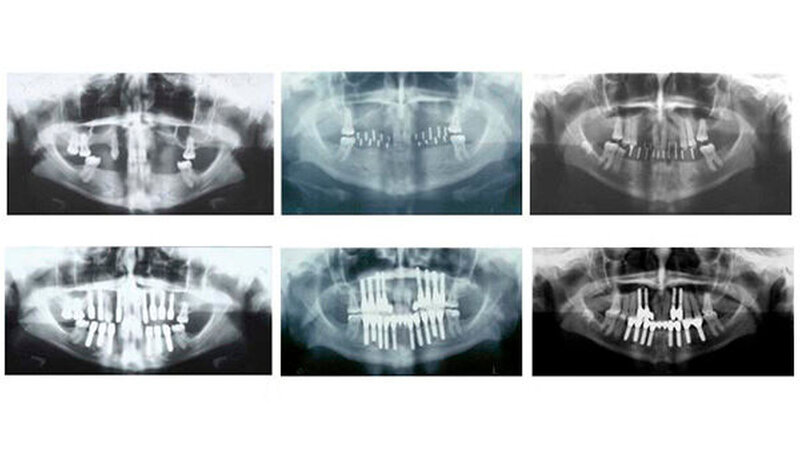

Zunächst entfernten die MKG-Chirurgen alle vorhandenen Milchzähne. Nach einer Abheilungsphase von rund zwölf Wochen wurde aufgrund der ausgeprägten Alveolarkammatrophie die umfangreiche horizontale Augmentation im Ober- und Unterkiefer mit körpereigenem Knochen vom Becken in Allgemeinnarkose durchgeführt. Nach sechs weiteren Monaten wurden insgesamt 43 Implantate inseriert und weitere drei Monate später erfolgte die Freilegung und das Weichteilmanagement.

Die definitive Prothetik wurde vier Monate später eingesetzt. Seither erfolgen regelmäßige Verlaufskontrollen und wichtige Hygienemaßnahmen. Auf den aktuellen Panoramaschichtaufnahmen, die bis zu 14 Jahre nach Abschluss der Behandlung erfolgten, stellt sich ein stabiles periimplantäres Knochenniveau bei allen drei Patientinnen dar. Die klinischen Untersuchungsparameter an sämtlichen Implantaten waren unauffällig. Sowohl in der Funktion als auch in der Ästhetik ist ein Langzeiterfolg zu verzeichnen.